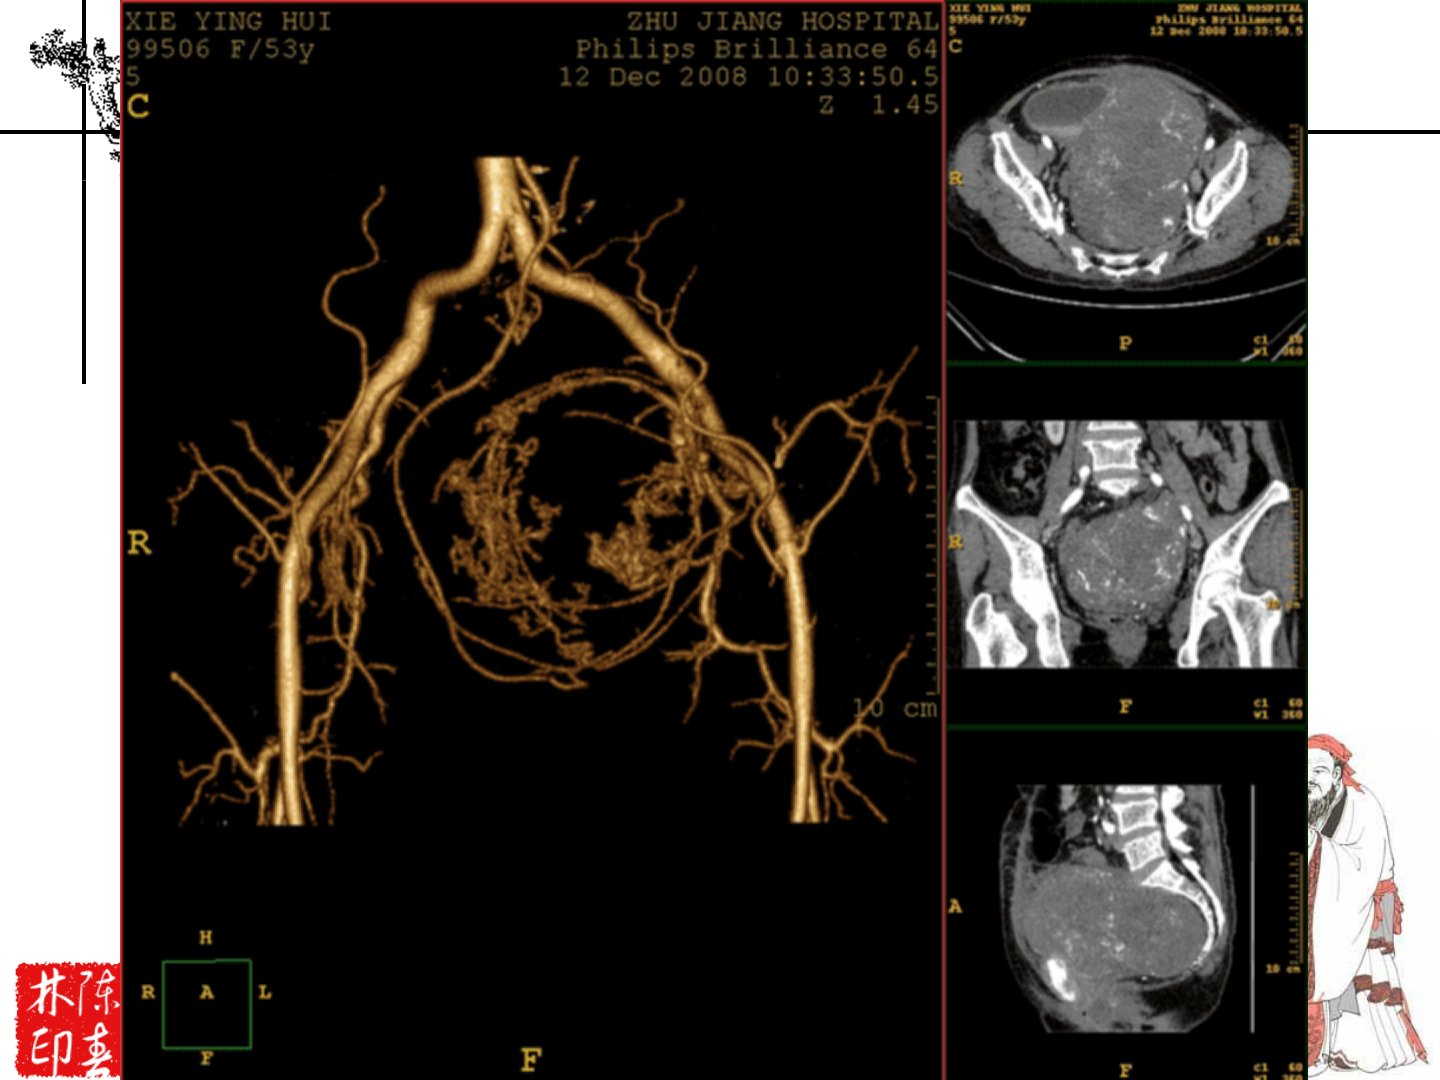

产后出血动脉治疗引入了新概念。子宫血供来自双侧子宫动脉和双侧卵巢动脉。动脉治疗包括结扎与栓塞两类:结扎有双侧髂内动脉、髂内动脉前干、子宫动脉、子宫动脉上行支及子宫动脉卵巢支结扎等;栓塞包括双侧髂内动脉、髂内动脉前干、子宫动脉、子宫动脉上行支及子宫动脉下行支栓塞等。其中动脉栓塞治疗起源于1979年Brown等完成的首例产后出血盆腔血管栓塞治疗案例国外报道成功率约97国内统计两年发表文献的有效率达965。对于特殊类型产后出血如宫缩乏力、胎盘植入等血管选择上多考虑子宫动脉或髂内动脉栓塞。栓塞药物首选新鲜明胶海绵颗粒禁用明胶海绵粉、碘油等钢圈需慎用。栓塞术后需清除宫腔积血继续应用抗生素、缩宫剂并观察性激素分泌预防宫腔粘连。